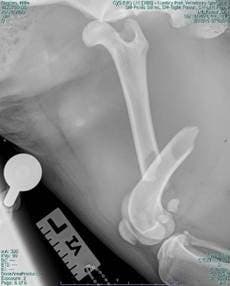

Millie was immediately stabilised with oxygen therapy along with intra-venous fluids to treat shock, and pain-relief. She underwent advanced imaging of her abdomen (CT imaging and radiography) to determine the severity of her injuries. This revealed Millie had sustained severe injuries, including trauma damage to her lungs, a severe hernia within her diaphragm, a fracture of the femur, and a hip dislocation.

Once Millie had been successfully treated by the soft tissue surgery team, it was time for Lumbry Park’s orthopaedic surgery Specialists to step in and perform a fracture repair to her femur and to stabilise her hip. The femoral fracture was stabilised using steel plates and screws, to ensure a strong and durable repair. Simultaneously, her hip dislocation was corrected and secured using a ‘hip toggle’ to restore the joint’s stability.

Lateral Xray of Millie’s femur fracture and hip dislocation